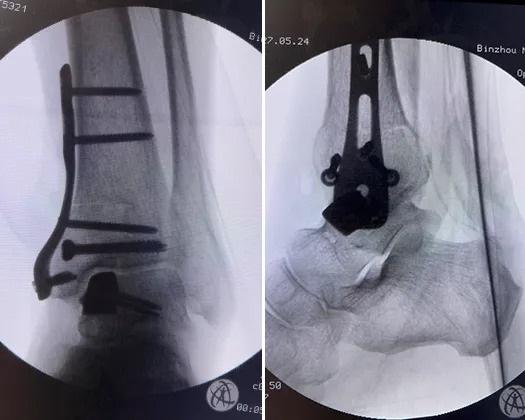

术后X线